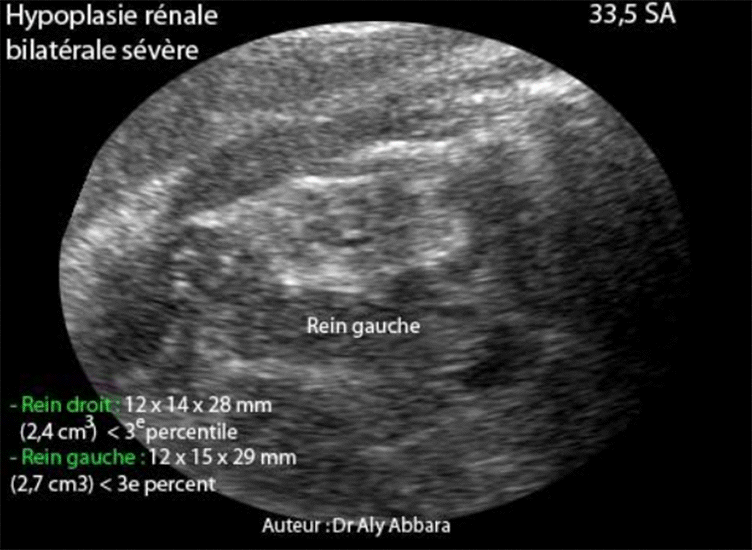

Hypoplasie rénale bilatérale à 33,5 SA - coupe échographique rénale antéro-postérieure

Hypoplasie rénale fœtale bilatérale et sévère découverte à 33,5 SA

Coupes échographiques antéro-postérieures des reins fœtaux hypoplasiques avec des images

échographiques permettant de les comparer aux reins normaux.

• Il s'agit d'une hypoplasie rénale fœtale bilatérale et sévère découverte fortuitement à 33,5 SA lors d'une exploration échographique dans le cadre du bilan systématique pour légère menace d'accouchement prématuré.

• L'échographie met en évidence la présence d'un anamnios avec deux petits reins hyper-échogènes :

• Rein gauche : 12 x 15 x 29 mm de diamètres avec volume évalué à (2,7 cm3) ce qui est largement inférieur au 3e percentile.

• Rein droit : 12 x 14 x 28 mm de diamètres avec volume évalué à (2,4 cm3) ce qui est largement inférieur au 3e percentile.